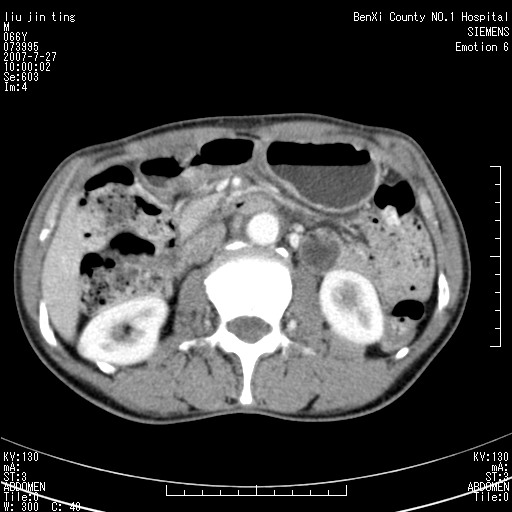

腹痛,背痛,无恶心呕吐,不黄,彩超示胰腺钩癌,ct扫描病灶平扫30-40hu,增强后动脉期40--60hu,静脉期50-68hu,真的是钩突上的么?您要试一试么?

动脉期

静脉期